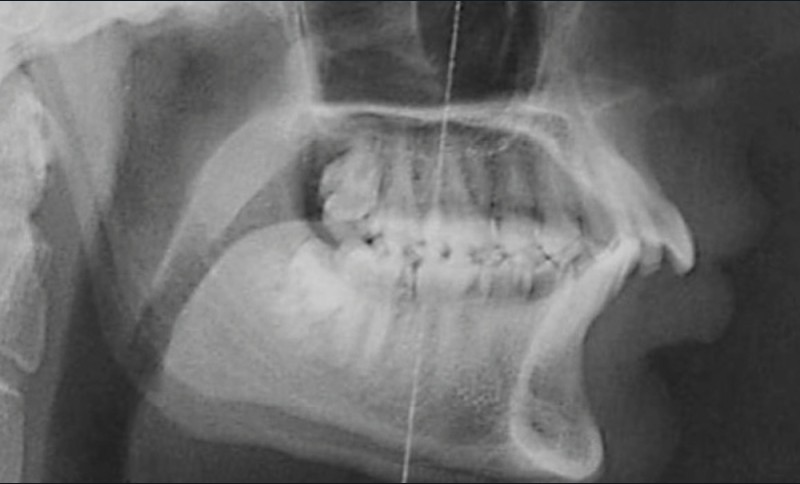

Le Dr Christophe Dunglas développera ensuite l’intérêt du cone beam lors de la mise en place des canines incluses difficiles. En effet, la préparation d’ancrages adéquats et de gestes chirurgicaux a minima préviendra l’apparition de résorptions radiculaires et de lésions parodontales.